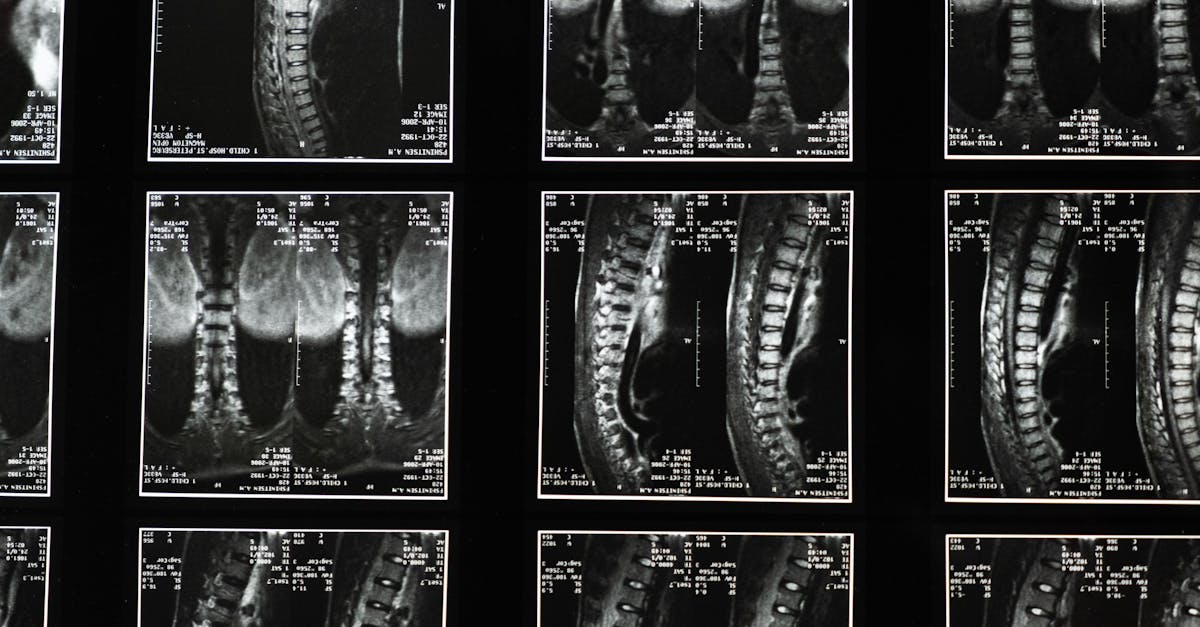

Relieve thoracic spine pain with Pulse Align’s innovative approach to enhancing movement and restoring balance. With studies showing that 80% of adults suffer from hyperlordosis, the link between poor posture and issues like upper back pain and muscle tension in the upper back is undeniable. This unique method targets common concerns such as pain between shoulder blades and that nagging dorsal pain, providing effective solutions like upper back pain relief through upper back pain exercises, proper lifting techniques, and the use of an ergonomic backpack. Discover how Pulse Align’s comprehensive strategies can foster posture correction and promote wellness in your daily life.

TAGMED’s neurovertebral decompression applies a controlled, progressive traction force to the spine. This innovative method increases the space between vertebrae, helping to reduce pressure on intervertebral discs and nerve roots. As a result, the therapy promotes better fluid circulation in the targeted area, which aids in lowering inflammation and relieving pain. This non-invasive solution effectively supports individuals suffering from chronic back issues, providing relief to those affected by conditions such as spinal stenosis and disc pinch.

This non-invasive approach to treating conditions like herniated discs or spinal stenosis can effectively alleviate chronic pain. By reducing pressure on nerve structures and optimizing fluid circulation around the discs, TAGMED’s neurovertebral decompression can fast-track recovery and enhance the quality of life for many patients seeking relief from persistent discomfort. Patients often find their mobility improved and a decrease in symptoms associated with conditions such as facet syndrome or degenerative disc disease.